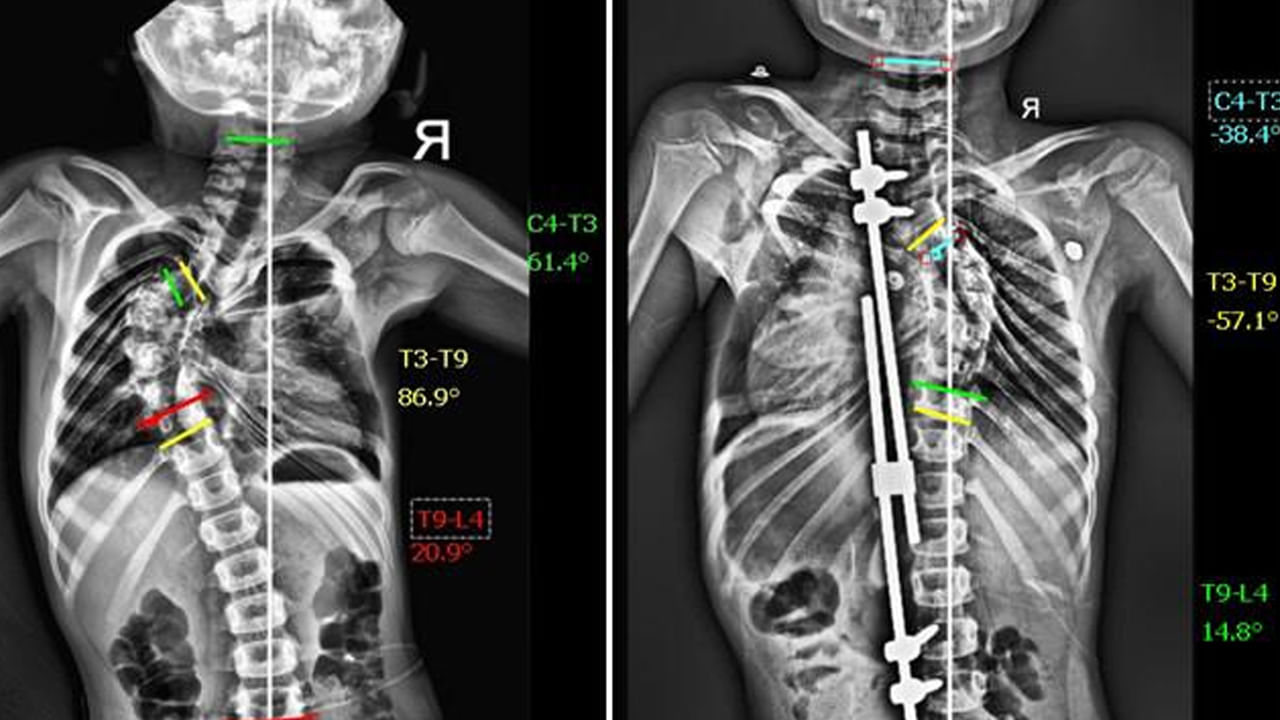

పాపకు పరీక్షలు చేయగా, ఆమె వెన్నుపూస 86 డిగ్రీల వక్రతతో ఉన్నట్లు తేలింది. ఇది “థొరాసిక్ స్కోలియోసిస్” అనే వ్యాధి, దాన్ని నిర్లక్ష్యం చేస్తే గుండె, ఊపిరితిత్తులకు సమస్యలు కలగవచ్చు. డాక్టర్ విద్యాధర రోబోటిక్ టెక్నాలజీ సాయంతో “గ్రోత్ రాడ్ సర్జరీ” చేయాలని సూచించారు. ఇది కేవలం వెన్నుపూస వక్రతను సరిచేయడం కాకుండా, అది సహజంగా పెరగడానికి కూడా సహాయపడుతుంది.

సక్సెస్ అయిన ఆపరేషన్

మే 1, 2025న ఆద్యకు సర్జరీ జరిగింది. అత్యాధునిక రోబోటిక్ టెక్నాలజీతో, ఆమె వెన్నుపూసను సున్నితంగా సరిచేయడం జరిగింది. శస్త్రచికిత్స పూర్తయిన మూడు గంటల్లోనే ఆద్య సపోర్ట్తో నడవగలిగింది. రెండు రోజుల్లోనే ఆమె ఆసుపత్రి నుంచి డిశ్చార్జ్ అయింది.